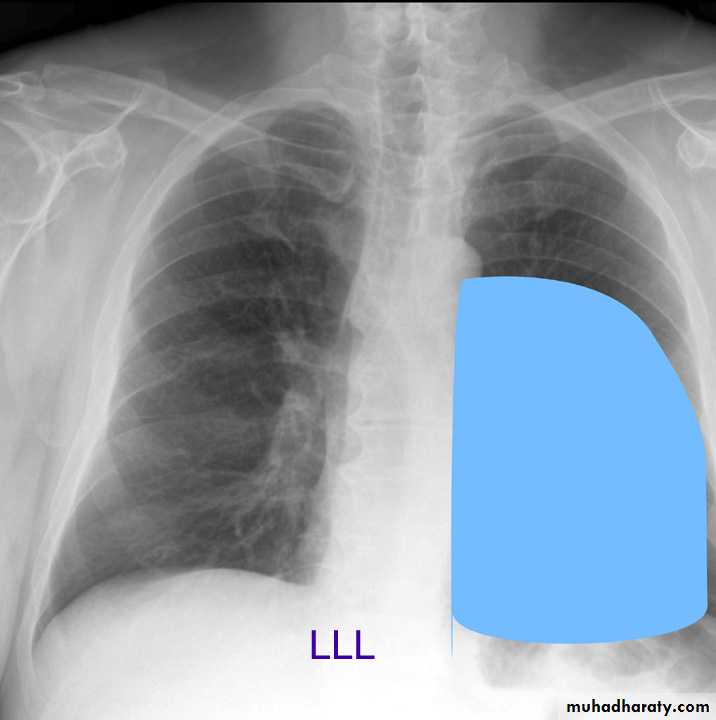

Lung Anatomy

Zonal anatomyLobar anatomy

Rt lung divided to 3 lobes (upper , middle & lower )

Transverse fissure separate the upper lobe from middle lobeOblique fissure separates the upper & middle from lower lobe .

The left lung subdivided to two lobes by oblique fissure ( upper & lower )

Left upper lobe

LUL collapse

Left lingula

Left lower lobe